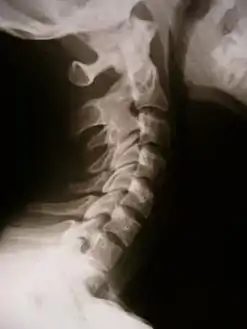

![]() صورة أشعة تظهر التحام العظام في فقار العنق صورة أشعة تظهر التحام العظام في فقار العنق | |